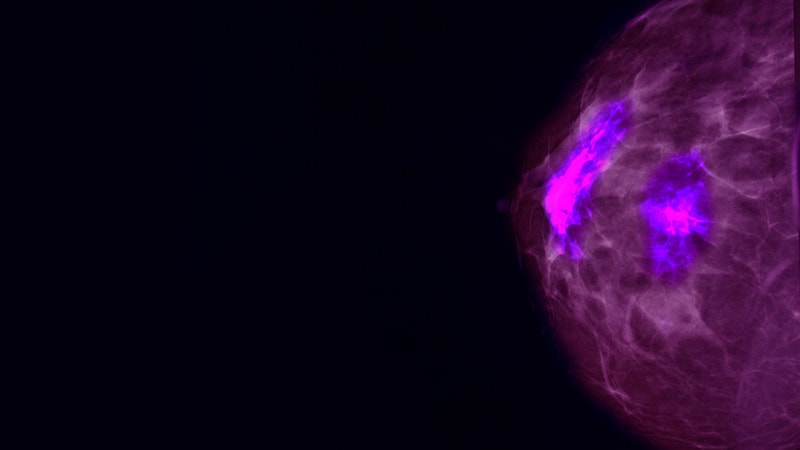

Metastatic Breast Cancer

Survival-Toxicity Trade-off With T-DM1 in HER+ Breast Cancer

HER2+ Combo Shows Promise in Breast Cancer Brain Mets